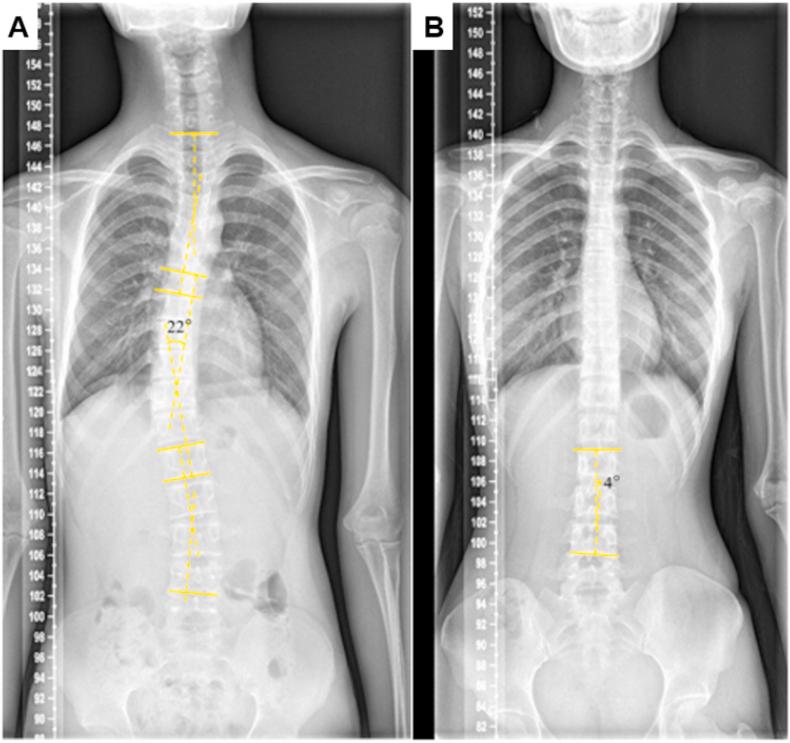

We designed a new portable electronic scoliosis screening device (PESSD)-for the identification of adolescent scoliosis based on ergonomics theory. The device measured the axial deflection angle of the trunk of the human body using a built-in angle sensor. Data obtained using the PESSD, a traditional scoliometer manual ruler, and X-ray measurement of the Cobb angle were compared.

The PESSD exhibited more sensitive detection of small-angle scoliosis and improved repeatability compared with the scoliometer. The data obtained using the PESSD showed good correlation with Cobb angle data measured from X-ray images. All patients who were indicated to be positive for scoliosis using the PESSD were found to have clinically identifiable scoliosis from X-ray examination.